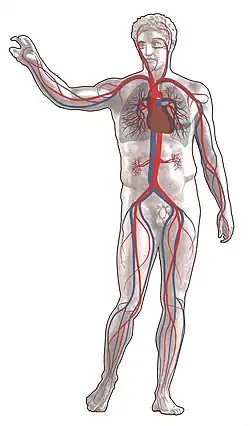

Серде́чно-сосу́дистая систе́ма (лат. systema cardiovasculare) — система органов, обеспечивающих циркуляцию крови в организме человека и животных. Благодаря её деятельности кислород и питательные вещества доставляются к органам и тканям тела, а углекислый газ, другие продукты метаболизма и отходы жизнедеятельности отводятся от органов и тканей и затем выводятся из организма.

В состав сердечно-сосудистой системы входит сердце и кровеносные сосуды. Сердце — мышечный орган, заставляющий кровь двигаться, ритмически нагнетая её в кровеносные сосуды — полые трубки различного диаметра, по которым происходит циркуляция крови.

Кровеносные сосуды — полые трубки, по которым движется кровь. Сосуды, несущие кровь от сердца к органам называют «артериями», а от органов к сердцу — «венами». В артериях и венах не осуществляется газообмен и диффузия питательных веществ, это просто путь доставки. По мере удаления кровеносных сосудов от сердца они становятся мельче. Существуют несколько классификаций сосудов: анатомическая, гистологическая, морфо-физиологическая.

Кровеносные сосуды делят на 3 типа: вены, артерии, капилляры. Артерии направляют кровь от сердца к другим органам, а вены наоборот — от органов к сердцу. Артерии имеют толстые эластичные стенки в связи с высоким давлением в сердце (до 250 мм ртутного столба), а вены — менее толстую.